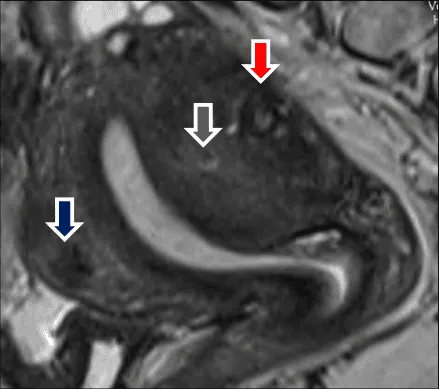

Hình ảnh “Cộng hưởng từ của adenomyosis”.

Tổn thương có thể khu trú tạo giả u xơ, hoặc kết hợp với u xơ thật, khó phân biệt.

Hình ảnh “Kết hợp adenomyosis và u xơ tử cung”.

MRI: Phân biệt adenomyosis vs u xơ, đánh giá lạc nội mạc sâu.